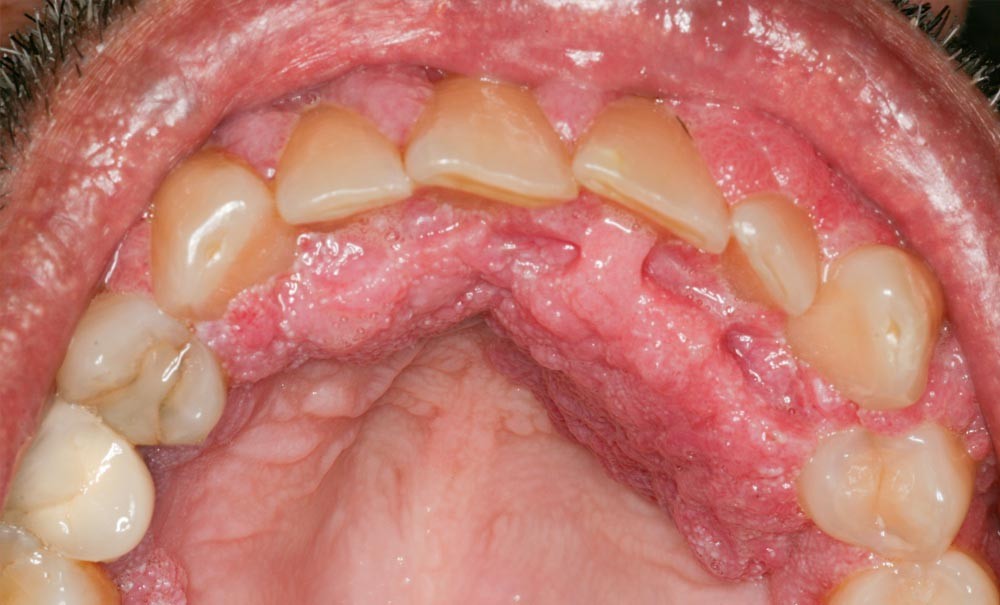

La candidose oro-pharyngée

C’est l’infection orale opportuniste la plus fréquente (17 à 75 % des patients selon les séries [2]) associée au candida albicans. Elle apparaît chez les sujets infectés par le VIH dont le taux de lymphocytes T CD4+ est inférieur à 200 cellules/mm3. Elle est considérée comme un facteur prédictif majeur…